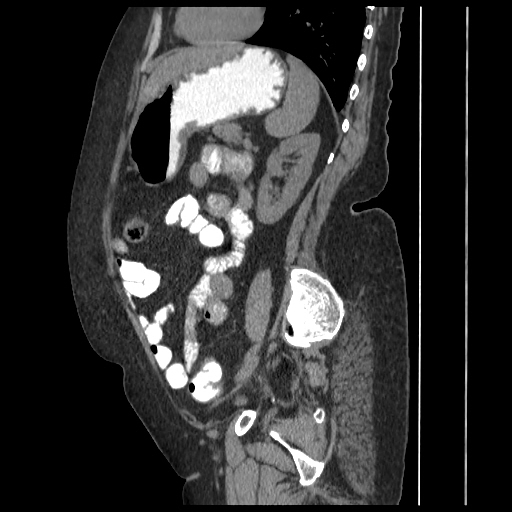

A 70 years old woman with Obstractive jaundice & palpable GB